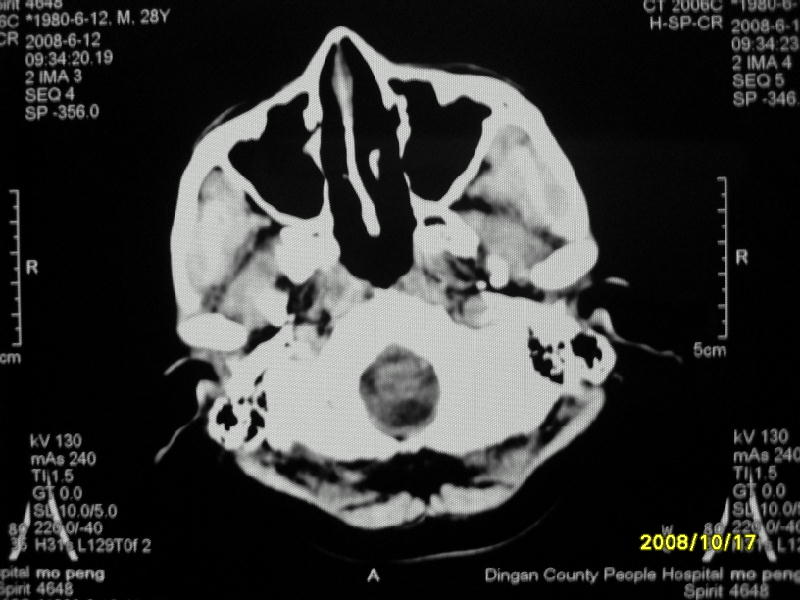

检查名称:     ct颅脑平扫           男     28岁

表现:左顶叶见斑点状致密影。边缘清,大小约0。3*1。0cm,余脑实质密度及灰白质结构示见异常。脑室系统大小,形态,密度未见异常。脑沟。脑裂。脑池未见异常密度影。中线结构无移位。

印象:左顶叶少许钙化灶